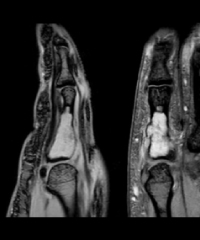

- 手指

画像診断、特に関節、骨軟部疾患、スポーツ医学、MRI